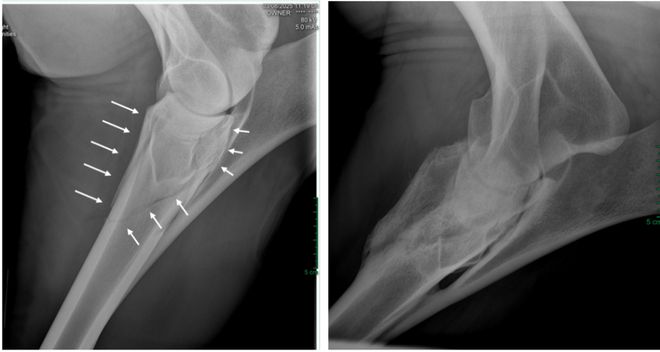

MK体育马一旦骨折真的就“没救了”吗?(图6)

踢伤造成的成年马桡骨骨折,外固定保守治疗,6个月后复查长出骨痂。图源:王炜晗